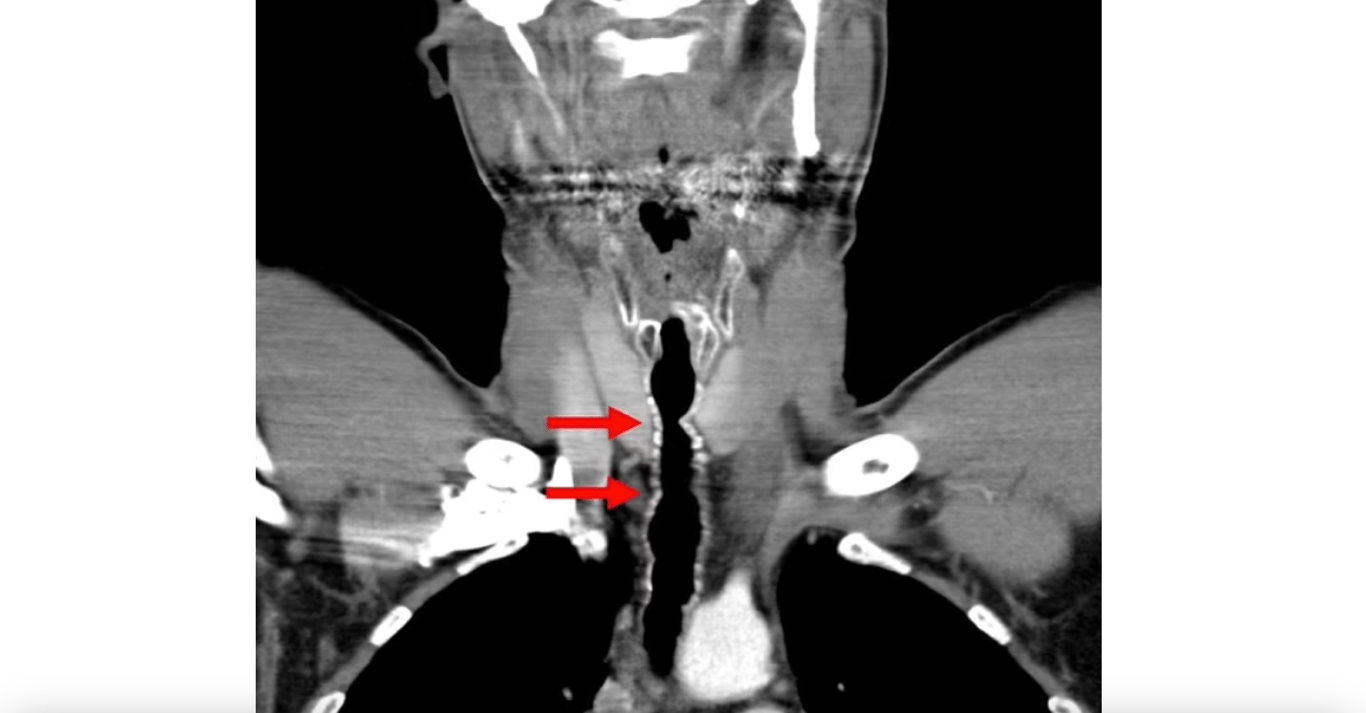

К счастью, больница была технологически оснащена, и врачи сразу отправили больного на исследования. Сначала сделали компьютерную томографию, обнаружив что-то довольно странное.

Волосы выросли в горле мужчины — врачи заявили, что причина в сигаретах

У мужчины выросли волосы в горле. Фото: Daily Mail